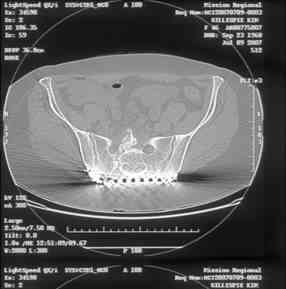

Re: Sacral Non-Union

David Zamorano 25 Август 2007, 21:05

Here is a magnified view. Sorry about the quality but the CT was scanned into our system.

dave

Отправитель: Chip Routt 25 Август 2007, 21:08

Thank you...it might help to remove the disengaged and other iliosacral screws then insert longer lag screws into the upper sacral segment and if anatomically feasible into the second sacral segment as well.

You could do it percutaneously and even add an electrical stimulation device if that seems reasonable.

At this point, I'd ignore the right pubic root issue if asymptomatic.

If simple measures such as those above fail, then you could remove it all, take down the sacral fracture site, refix with alternate techniques, and bone graft.

Chip